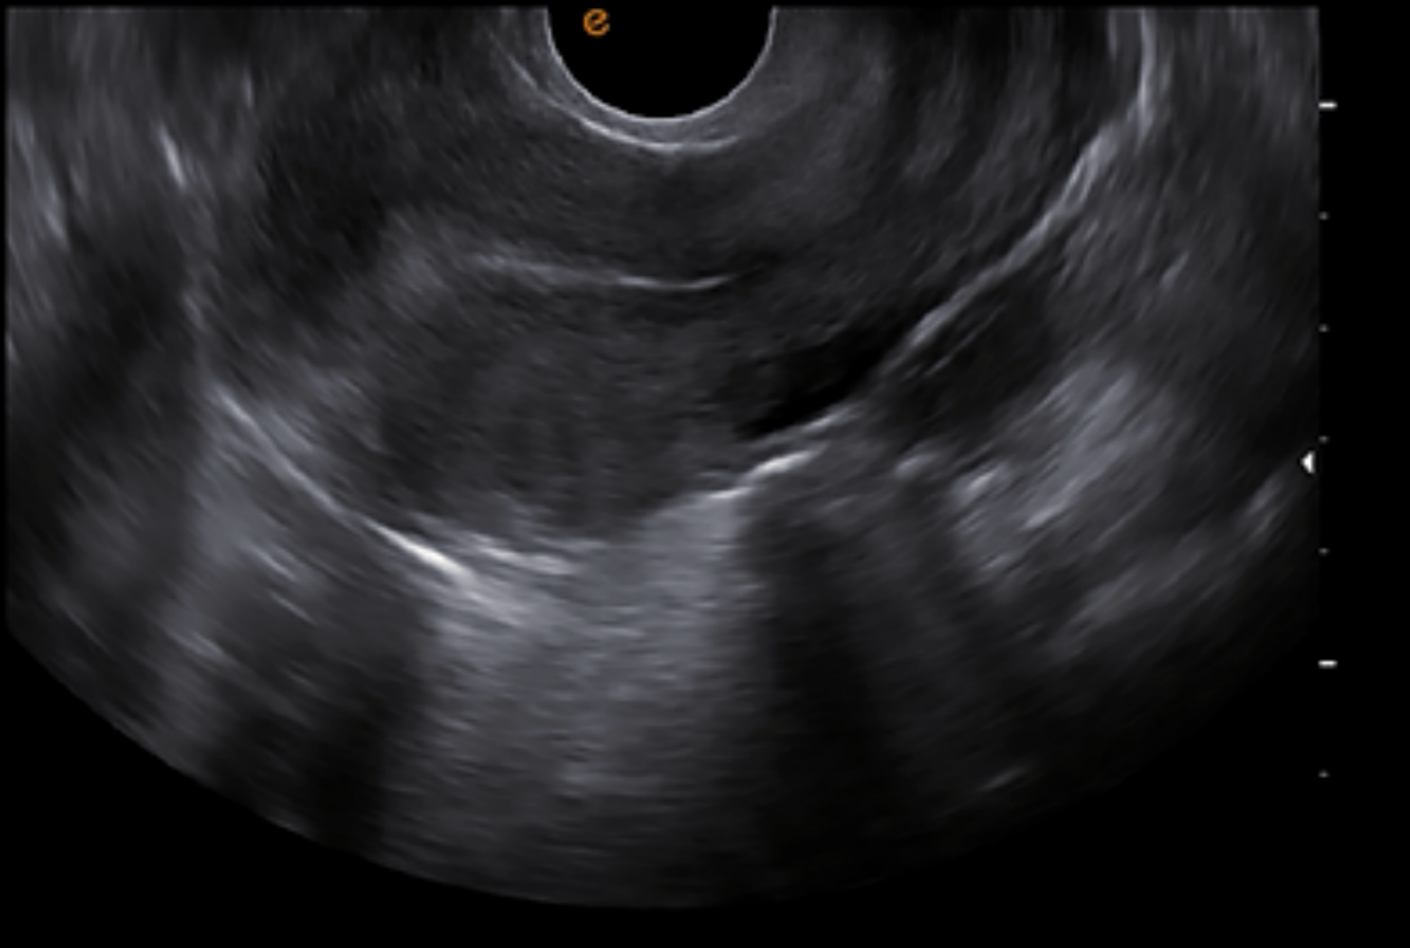

เครื่องอัลตราซาวด์ Doppler สีแบบพกพา สำหรับสัตวแพทย์ มาพร้อมกับแพลตฟอร์มเทคโนโลยีที่มีประสิทธิภาพสูง หัวตรวจหลากหลายรูปแบบ สามารถแสดงภาพรอยโรคที่ซับซ้อนได้อย่างชัดเจน และซอฟต์แวร์การวัดผลที่ผ่านการตรวจสอบทางคลินิกแล้ว ทำให้เครื่องนี้เป็นผู้ช่วยสำหรับการวินิจฉัยพื้นฐานในสถานพยาบาลสัตวแพทย์ได้อย่างแม่นยำและสะดวกสบาย